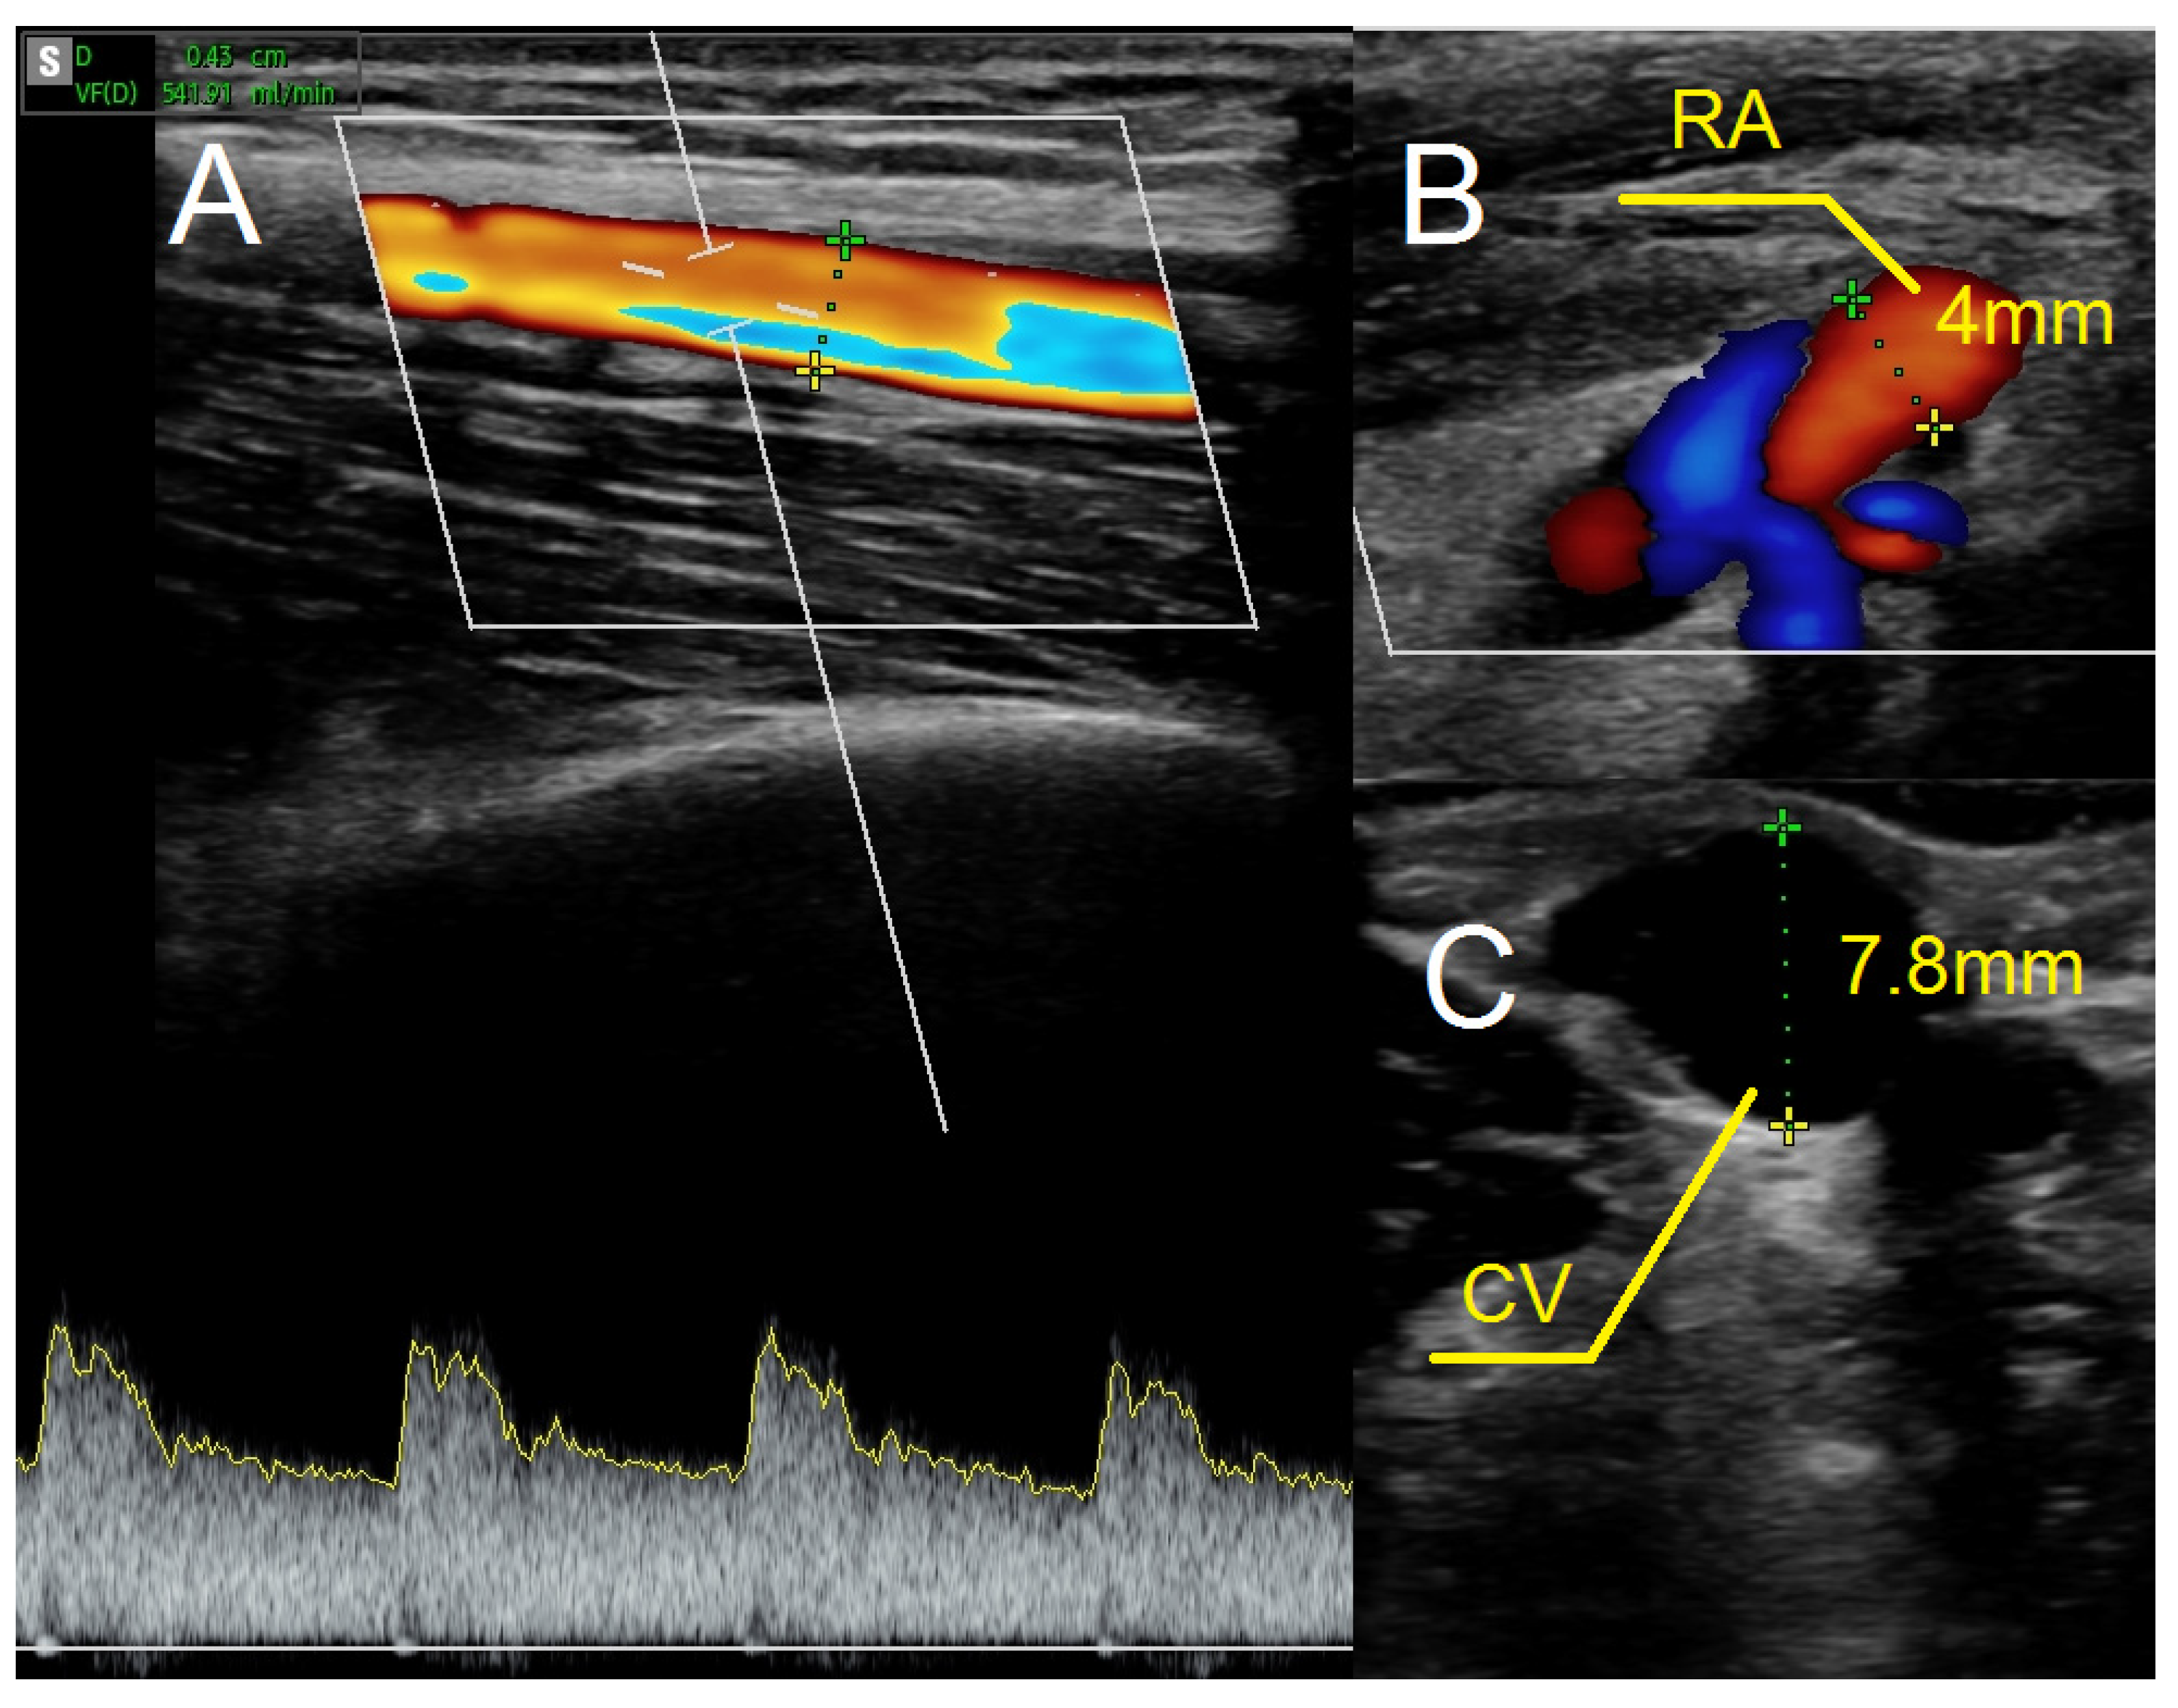

As in previous cases, the surgical site was determined by the results of the ultrasound examination. In the present case, the patent artery was found in the third proximal of the forearm (Figure 5A). The procedure was carried out as described above. In this case, however, the vein and artery were in close proximity to one another, which is why Option II for anastomosis was chosen. After performing an anastomosis and releasing the clamps, we detected a blood flow in the vessel (Figure 5B). The following day’s ultrasound examination of the fistula revealed a flow rate of 541 mL/min (Figure 6A). The diameter of the radial artery (Figure 6B) and the cephalic vein (Figure 6C) also increased to 4 mm and 7.8 mm, respectively. The patient was given salicylic acid in the postoperative period, despite having taken this medication prior to creating a fistula due to antiphospholipid syndrome. One month later, the fistula was successfully cannulated.

Figure 6.

Ultrasound examination after creating the fistula using the RADAR technique. (A) Fistula flow measured on brachial artery. (B) Doppler ultrasound—a longitudinal section of the radial artery. (C) The cephalic vein in cross-section at the cubital fossa. Abbreviations: RADAR—radial artery deviation and reimplantation, RA—radial artery, CV—cephalic vein.